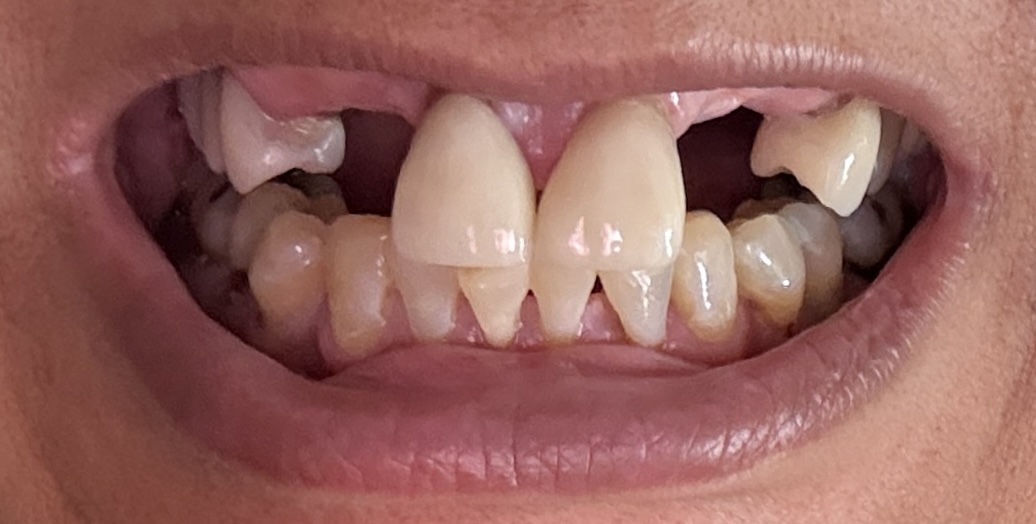

Overall information (upper arch)

12,13,14 have had root canals in past and now have quite a bit movement. 2-5 have all had root canals in past and now the crowns are breaking down.